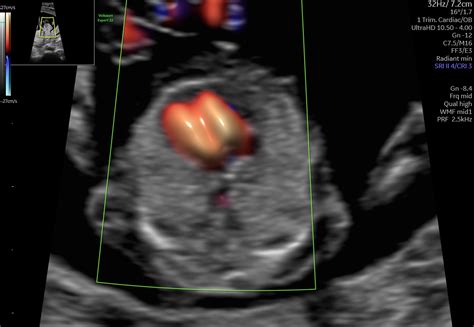

2D, 3D a 4D Ultrazvuk

- 2D Ultrazvuk: Je hlavný diagnostický nástroj pri ultrazvukovom vyšetrovaní a stačí na zistenie všetkých potrebných údajov o plode.

- 3D Ultrazvuk: Predstavuje statické zobrazenie plodu v priestore. Trojrozmerný obraz sa dosahuje počítačovým spracovaním súboru nakumulovaných 2D obrazov.

- 4D Ultrazvuk: Líši sa od 3D obrazu faktorom času/pohybu. Umožňuje sledovať, ako sa dieťa hýbe a sledovať jeho mimiku v priamom prenose.

Základné povinné prenatálne ultrazvuky sa robia 2D formou, čo je dostatočné na získanie potrebných údajov.

- Vývoj orgánov: Skúma sa vývoj a štruktúra orgánov, ako sú mozog, srdce, obličky, pľúca, žalúdok a črevá.

- Prítomnosť vrodených chýb: Ultrazvuk môže odhaliť niektoré vrodené vývojové chyby, ako sú rázštepy, anomálie končatín alebo srdcové vady. Môže odhaliť aj počet prstov na rukách a ich vyvinutie, alebo anomálie na srdci.